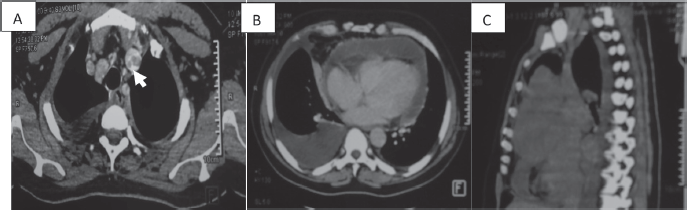

Figure 2. CT scan of a 58-year-old man (a): Cross-section of brachiocephalic trunk thrombosis (white arrow). (b): Cross-section of right pericardial and pleural effusion. (c): Sagittal section with a mediastinal mass.